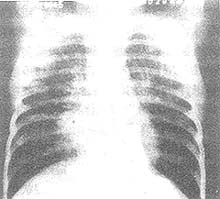

X線胸片顯示不呈段或葉性分布的周圍片狀陰影,常為雙側分布(“肺水腫反轉”表現)。糖皮質激素治療後48小時內症狀和X線表現可迅速消失。在同一局部可反覆發生,數年後變為纖維化或蜂窩狀改變。胸部X片顯示不呈段或葉性分布的周圍片狀陰影,常為雙側分布。糖皮質激素治療後48h內症狀和胸片可迅速消失。在同一局部可反覆發生,數年後變為纖維化或蜂窩狀改變。糖皮質激素治療效果顯著,常可恢復正常,因停藥較易復發,故全療程需在一年以上。

其他輔助檢查:X線表現:大葉實變、小葉浸潤、膿腫形成。大葉實變多位於右上葉,由於炎性滲出物量多,黏稠且重,故葉間裂呈弧形下墜。炎症浸潤中見膿腫,胸腔積液,少數呈支氣管肺炎。